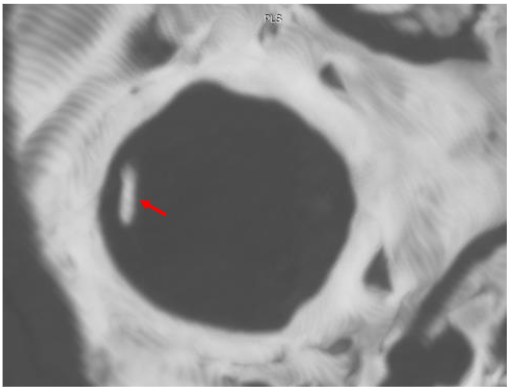

This case report describes a patient with chronic neck pain following cervical spine manipulation techniques. The patient presented with significant neurological symptoms on both sides of the neck, caused by combined end-range cervical rotation and extension. We decided not to proceed with axial MRI in these cases. We followed up with an axial view, which showed…

We positioned the cervical spine in a rotated position, and the findings showed that the C1-2 segment placed under tension. The MRI results indicated a cross-sectional lesion to the Anterior Longitudinal Ligament illustrated in Figure 10.